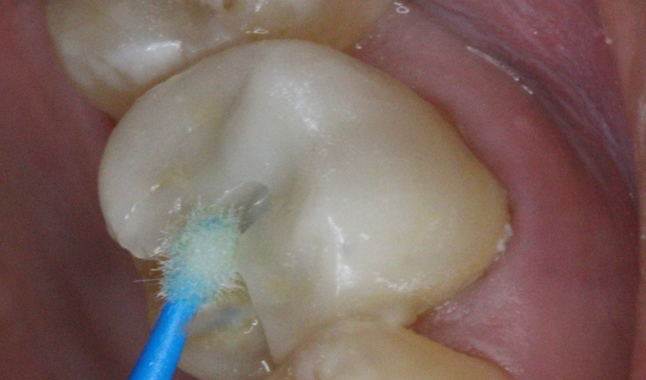

Universal adhesive acting as a silane being applied to internal aspect of indirect ceramic restoration prior to cementation.

We began with our indirect restoration (crown) in the upper left. The temporary was removed and the surface was treated with an antimicrobial. After a try-in where margins and contacts were verified, we treated the internal aspect of the ceramic with a universal adhesive [Futurabond U; VOCO] to allow for the use of a resin cement [Duo-Link Universal; BISCO] (the intaglio had been etched and sandblasted by the technician at the lab).